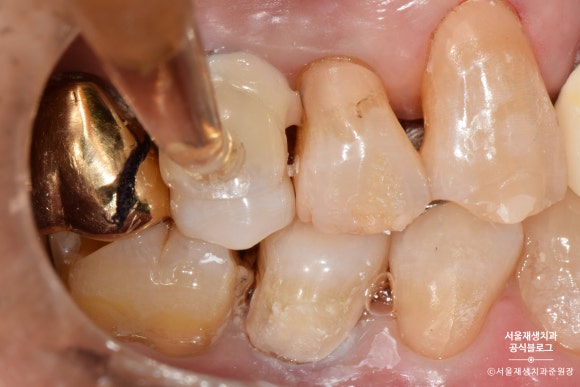

레진을 한 겹, 한 겹 정성껏 쌓아올립니다.

이때, 침이나 물 한방울도 튀지 않도록 조심!

들뜬 자리가 없도록 꼼꼼하게 레진을 다듬어줍니다.

사진상으로는 모두 나오지 않지만,

반질반질하고 심미적인 결과를 위해서

여러번의 마무리 과정을 거치게 됩니다.